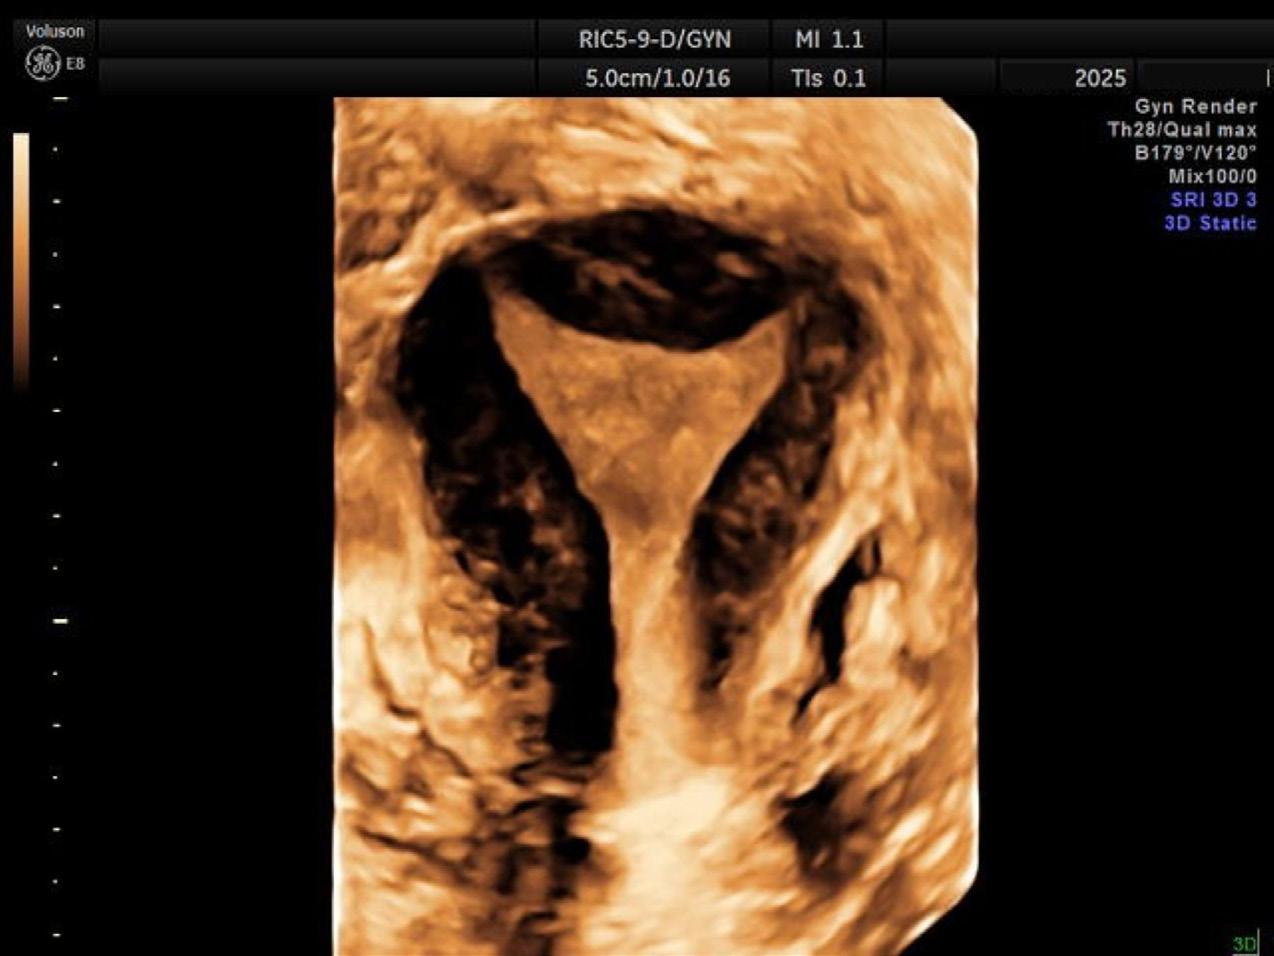

4. Les avancées technologiques et leurs impacts

En un simple balayage de sonde, la machine d’échographie dotée d’algorithmes avancés peut nous donner beaucoup d’informations pertinentes et même nous en faire des rendus 3D. La reconstruction d’images nous permet d’évaluer la cavité utérine en 3D (Figure 4). C’est une image très importante à obtenir, puisqu’elle peut démontrer des variantes anatomiques utérines qui peuvent impacter la fertilité d’une patiente. C’est l’une des images clés

que l’on prend à la Clinique ovo, lors de l’échographie de réserve ovarienne.